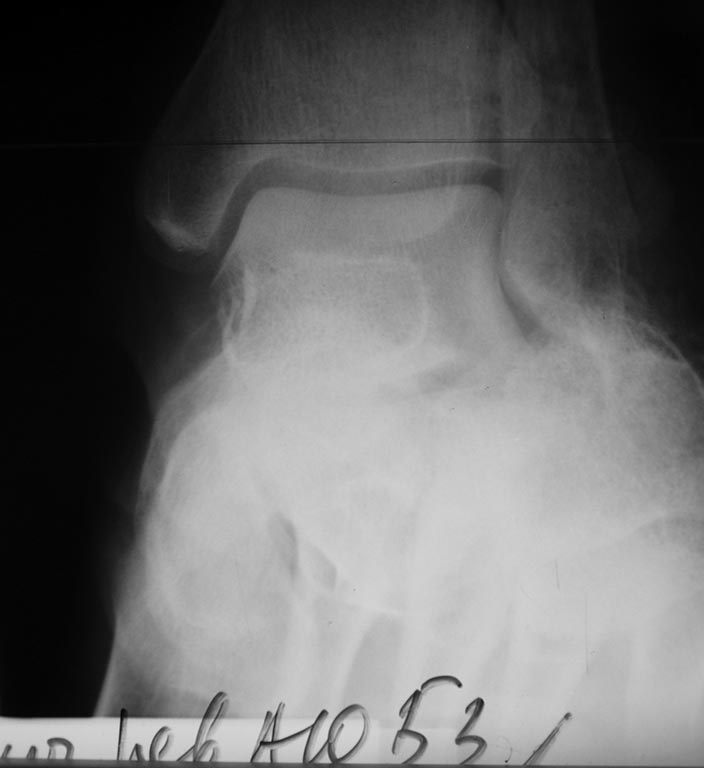

Пациента прооперировал 5 мая. Произвел аутопластику костной крошкой и фиксацию спицами. Выкладываю снимки

наружная лодыжка целая. Хотелось бы устранить оставшуюся импрессию суставной фасетки и еще низвести бугор из доступа в проекции подтаранного сустава, чтобы в последующем избежать уплощения свода. Мягкие ткани снаружи интактны, но в области раны с медиальной стороны сохраняется небольшое количество геморрагического отделяемого.